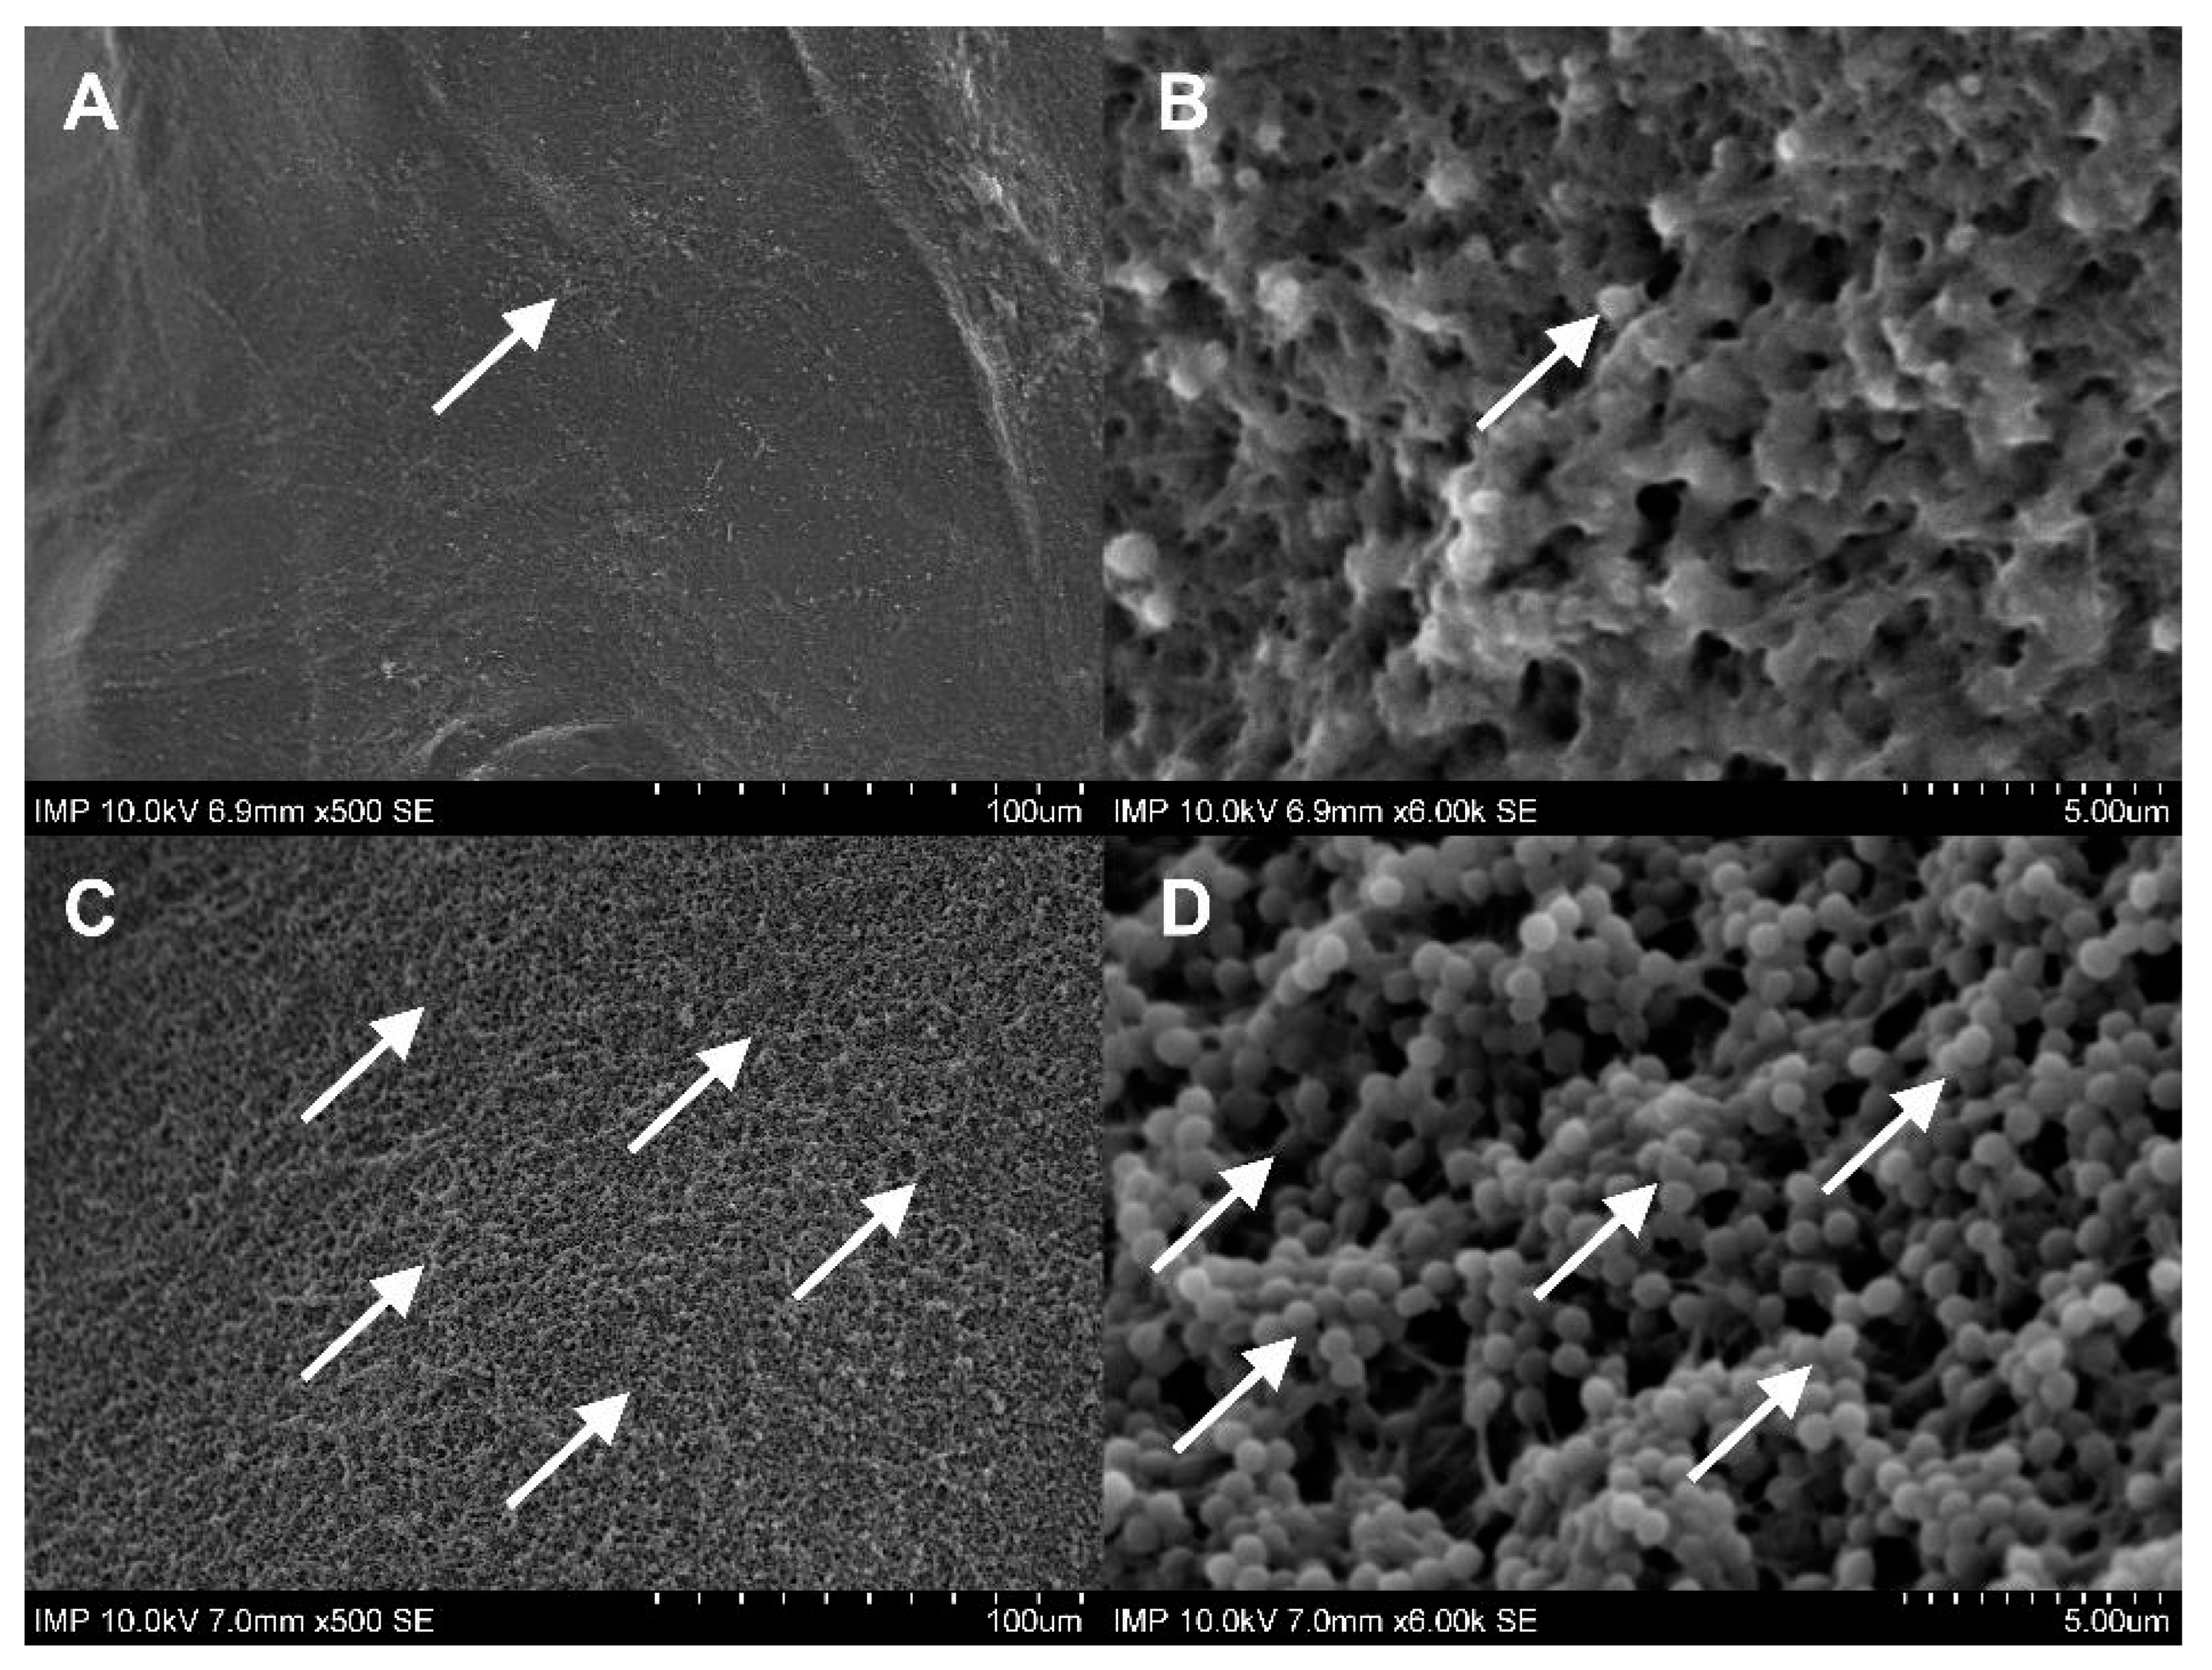

2.1. Surface Coating of the Grafts

4.2.5. Scanning Electron Microscopy